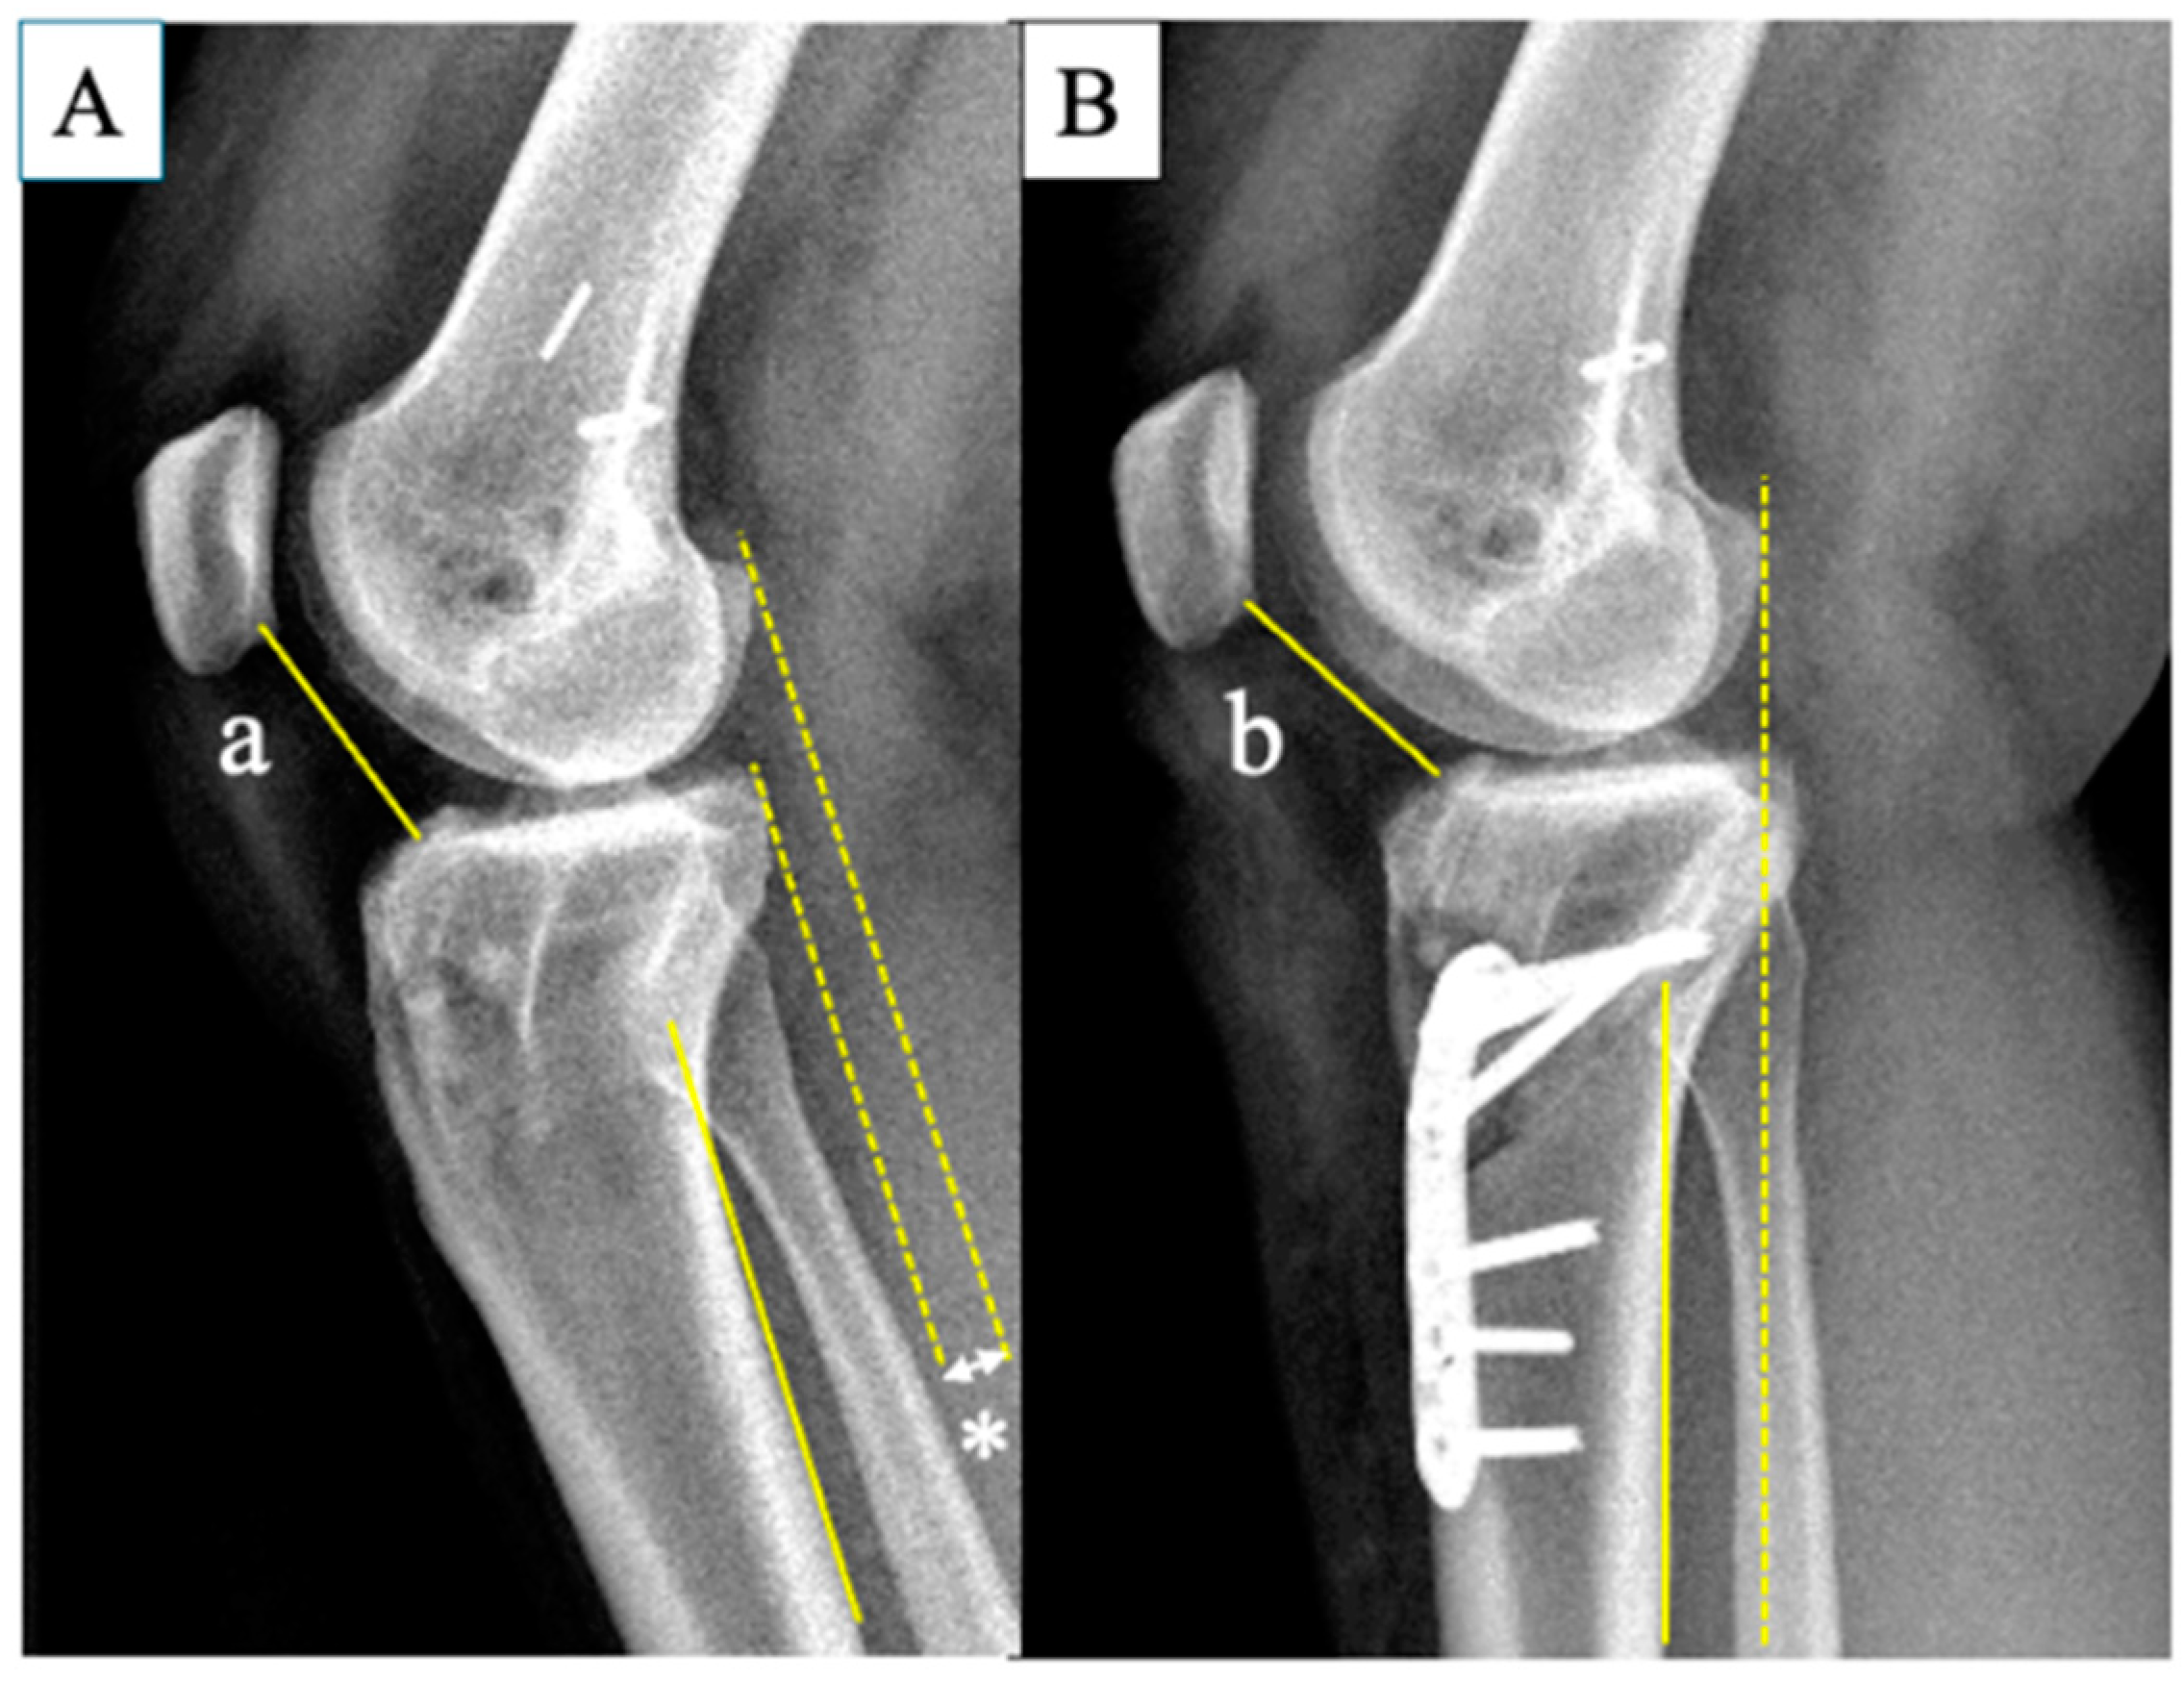

2.2. Surgical Options and Procedures

2.4. Radiographic Measurements and Clinical Outcomes